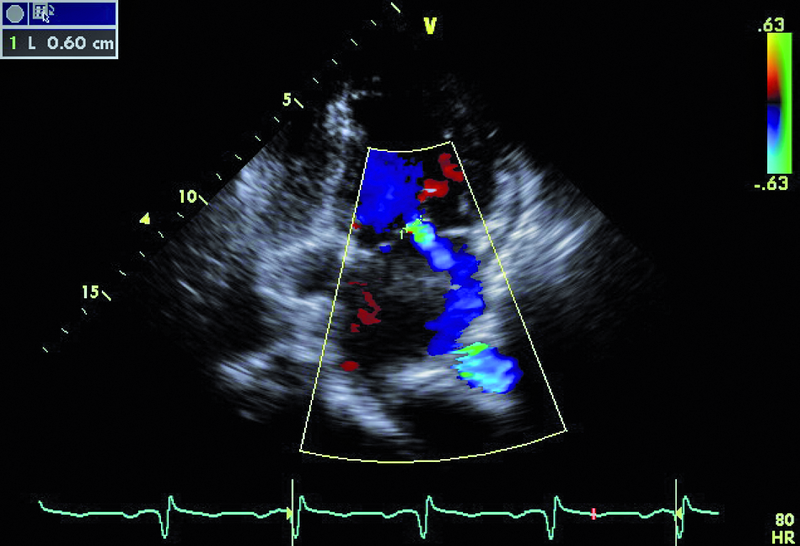

U chłopca, obecnie 16-letniego, wykonano w okresie noworodkowym zabieg operacyjny walwuloplastyki zastawki aortalnej z powodu wrodzonej stenozy. Uzyskano zmniejszenie gradientu maksymalnego z 50 do 16 mm Hg. W ciągu wielu lat obserwacji w ośrodku kardiologii dziecięcej gradienty przepływu przez zastawkę były niskie, a stan kliniczny pacjenta dobry. Sytuacja zmieniła się przed kilkoma miesiącami. Chłopiec został przyjęty do szpitala z powodu męczliwości, szybkiej częstości serca (do 90/min w rytmie zatokowym z pojedynczą ekstrasystolią komorową). Prawdopodobną przyczyną pogorszenia stanu zdrowia była przebyta wcześniej infekcja górnych dróg oddechowych. W badaniu przedmiotowym zwracał uwagę szmer holosystoliczny na koniuszku, promieniujący do pachy. W EKG rejestrowano cechy przerostu i przeciążenia mięśnia lewej komory. Wykonano cewnikowanie serca, stwierdzając nadciśnienie płucne ze średnim ciśnieniem w kapilarach płucnych 29 mm Hg. Pacjent był leczony intensywnie lekami moczopędnymi, beta-adrenolitykami i amiodaronem. Wobec braku poprawy skierowano go na oddział kardiologii dorosłych w celu rozważenia wskazań do leczenia operacyjnego. W badaniu echokardiograficznym zwracały uwagę wąskie strumienie niedomykalności zastawki aortalnej z czasem PHT wynoszącym 206 ms, istotnie powiększona jama lewego przedsionka z powierzchnią około 50 cm2, ciężkie nadciśnienie płucne z ciśnieniem skurczowym w jamie prawej komory 114 mm Hg!, rejestrowanym z małej fali zwrotnej trójdzielnej. Nie stwierdzono wady przeciekowej.

Chłopiec przebył w okresie noworodkowym zabieg walwuloplastyki aortalnej powikłany niedomykalnością zastawki (ryc. 1). Wada miała charakter przewlekły i spowodowała pojawienie się mechanizmów wyrównawczych. Jednym z nich jest zwiększenie objętości lewej komory i przyspieszenie rytmu serca. Frakcja wyrzutowa lewej komory jest zachowana (ryc. 2). Z pewnością infekcja górnych dróg oddechowych była czynnikiem inicjującym niekorzystny dla chorego przebieg zdarzeń. Ocena ciężkości niedomykalności aortalnej na podstawie parametrów ilościowych jest w tym przypadku trudna. Czas połowicznego spadku gradientu ciśnień PHT (aorta – lewa komora) oraz strumień fali zwrotnej w badaniu kolorowego doplera mogłyby wskazywać na umiarkowaną niedomykalność. Nie można jednak zapominać o możliwości zwiększenia ciśnienia rozkurczowego w jamie lewej komory, istotnie zmniejszającego gradient wsteczny i zakres fali zwrotnej. W przypadku dwustrumieniowej fali zwrotnej (jak w tym przypadku) talii cząstkowych niedomykalności nie sumuje się. Podobnie ograniczone zastosowanie w tym wypadku (ekscentryczne fale zwrotne) ma metoda ERO. Najprawdopodobniej wtórną do niedomykalności aortalnej wadą jest niedomykalność mitralna wynikająca z poszerzenia jamy lewej komory i poszerzenia pierścienia zastawki mitralnej. Niedomykalność mitralna także wydaje się co najwyżej umiarkowana (ryc. 3). Należy pamiętać, że i w tym wypadku szerokość strumienia fali zwrotnej zależy od wysokości ciśnienia w jamie przyjmującej, czyli w lewym przedsionku. Na podstawie przedstawionego materiału (ryc. 4-6) można stwierdzić, że nadciśnienie płucne u chłopca (postkapilarne) jest ciężkie, a ciśnienia uległy istotnemu zwiększeniu w porównaniu z wartościami stwierdzanymi wcześniej podczas cewnikowania serca (ciśnienie rozkurczowe płucne 54 mm Hg, średnie 74 mm Hg!). Warto zwrócić uwagę na profil spływu z żył płucnych. Zaznacza się w nim bardzo krótka faza odzwierciedlająca wyłącznie rozkurczowy napływ krwi do lewego przedsionka. Zwiększona objętość jamy przedsionka, wysokie ciśnienie krwi w niej panujące oraz ograniczona podatność ściany sprawiają, że w fazie skurczu komory nie rejestruje się napływu do jamy przedsionka. Podobnie bardzo wysokie ciśnienie w układzie żył płucnych sprawia, że nie obserwuje się przepływu wstecznego w związku z ciągle zachowanym skurczem przedsionka (rytm zatokowy). Chłopca zakwalifikowano do operacji dwuzastawkowej z powodu ciężkiej niedomykalności aortalnej i mitralnej. Zabieg implantacji zastawki biologicznej o średnicy 23 mm w ujście aortalne oraz pierścienia o średnicy 32 mm w ujście mitralne przyniósł dobry efekt.